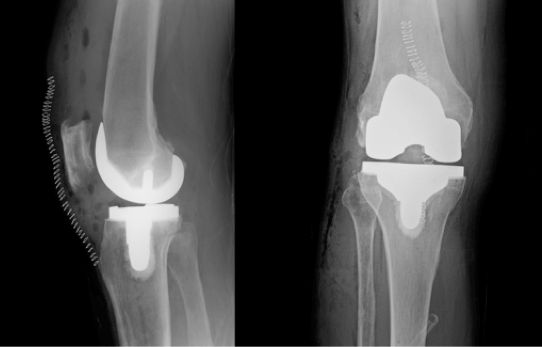

Based on the severity of the arthritis in the knee, total or partial knee replacement may be recommended by a surgeon. Both procedures involve the orthopaedic surgeon guiding the Mako Robotic-Arm to remove diseased bone and cartilage.

Mako Robotic-Arm Assisted Partial Knee replacement is a treatment option for adults living with early to mid-stage osteoarthritis (OA) that has not yet progressed to all three compartments of the knee.

In comparison, Mako Robotic-Arm Assisted Total Knee replacement is a treatment option for adults living with mid to late-stage osteoarthritis of the knee. With Mako Total Knee replacement, the entire knee joint is replaced and the surgeon inserts a Triathlon Total Knee implant. With over a decade of clinical history, Triathlon knee replacements are different than traditional knee replacements because they are designed to work with the body to promote natural-like circular motion.